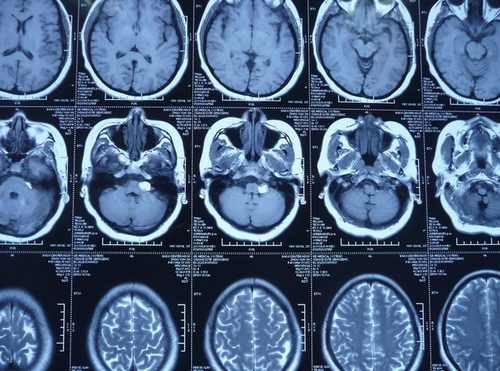

小脑脂肪瘤又称为颅内脂肪瘤”,是指在神经中枢里的某些胚胎组织出现异变而导致的一种脂肪性的组织肿瘤。这样的疾病是非常少见的临床现象。那么小脑长脂肪瘤究竟是什么导致的,是否有成熟的治疗技术进行根治?一起来看看吧。